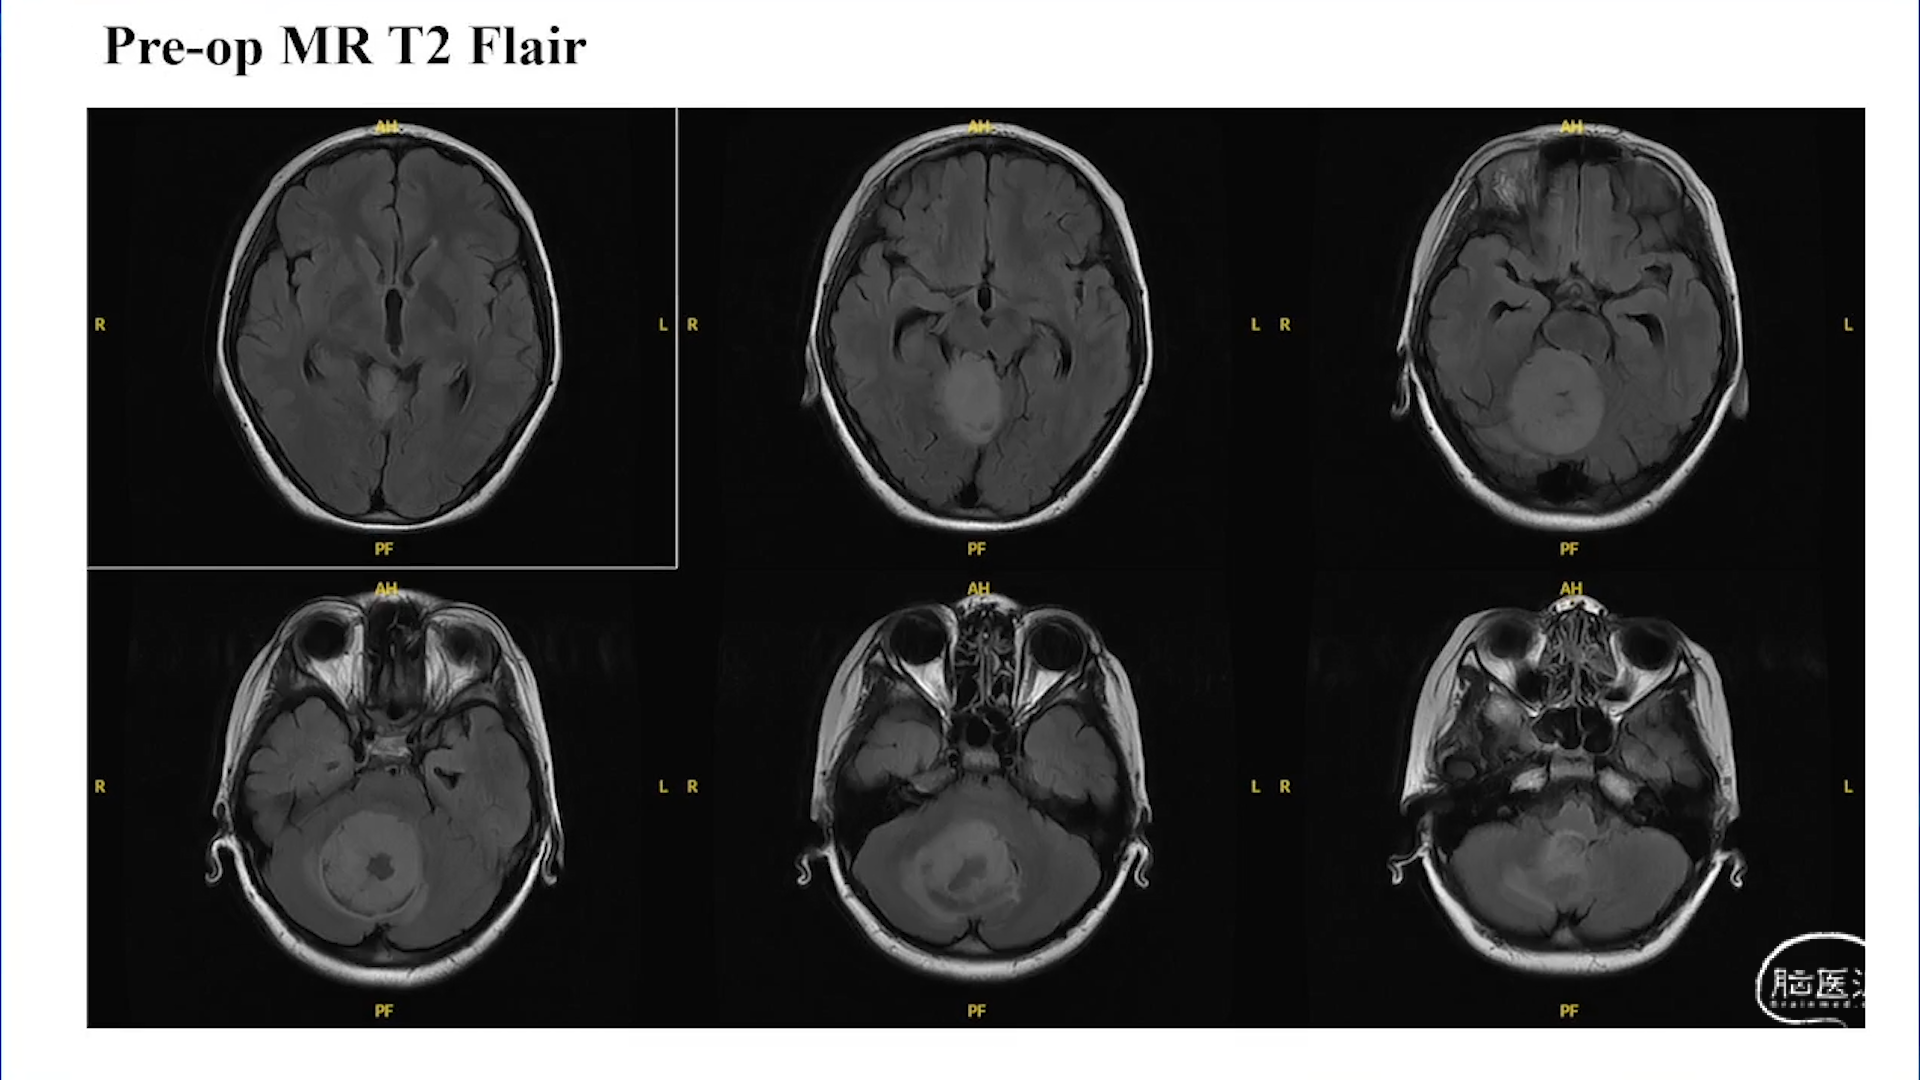

小脑星形细胞肿瘤